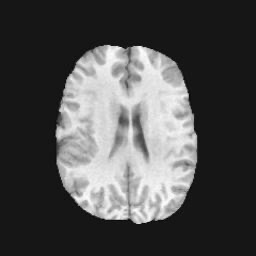

Denoising diffusion probabilistic models (DDPMs) have achieved unprecedented success in computer vision. However, they remain underutilized in medical imaging, a field crucial for disease diagnosis and treatment planning. This is primarily due to the high computational cost associated with (1) the use of large number of time steps (e.g., 1,000) in diffusion processes and (2) the increased dimensionality of medical images, which are often 3D or 4D. Training a diffusion model on medical images typically takes days to weeks, while sampling each image volume takes minutes to hours. To address this challenge, we introduce Fast-DDPM, a simple yet effective approach capable of improving training speed, sampling speed, and generation quality simultaneously. Unlike DDPM, which trains the image denoiser across 1,000 time steps, Fast-DDPM trains and samples using only 10 time steps. The key to our method lies in aligning the training and sampling procedures. We introduced two efficient noise schedulers with 10 time steps: one with uniform time step sampling and another with non-uniform sampling. We evaluated Fast-DDPM across three medical image-to-image generation tasks: multi-image super-resolution, image denoising, and image-to-image translation. Fast-DDPM outperformed DDPM and current state-of-the-art methods based on convolutional networks and generative adversarial networks in all tasks. Additionally, Fast-DDPM reduced training time by a factor of 5 and sampling time by a factor of 100 compared to DDPM. Our code is publicly available at: https://github.com/mirthAI/Fast-DDPM.